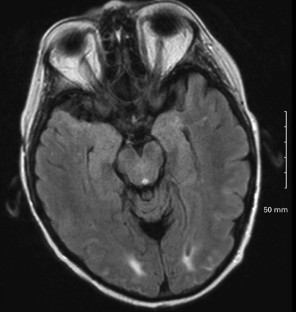

Sukumaran, S., George, B., Nair, H. et al. Posterior reversible encephalopathy syndrome as a consequence of high dose steroid administration after autologous PBSCT. Bone Marrow Transplant 45, 779–780 (2010). https://doi.org/10.1038/bmt.2009.211